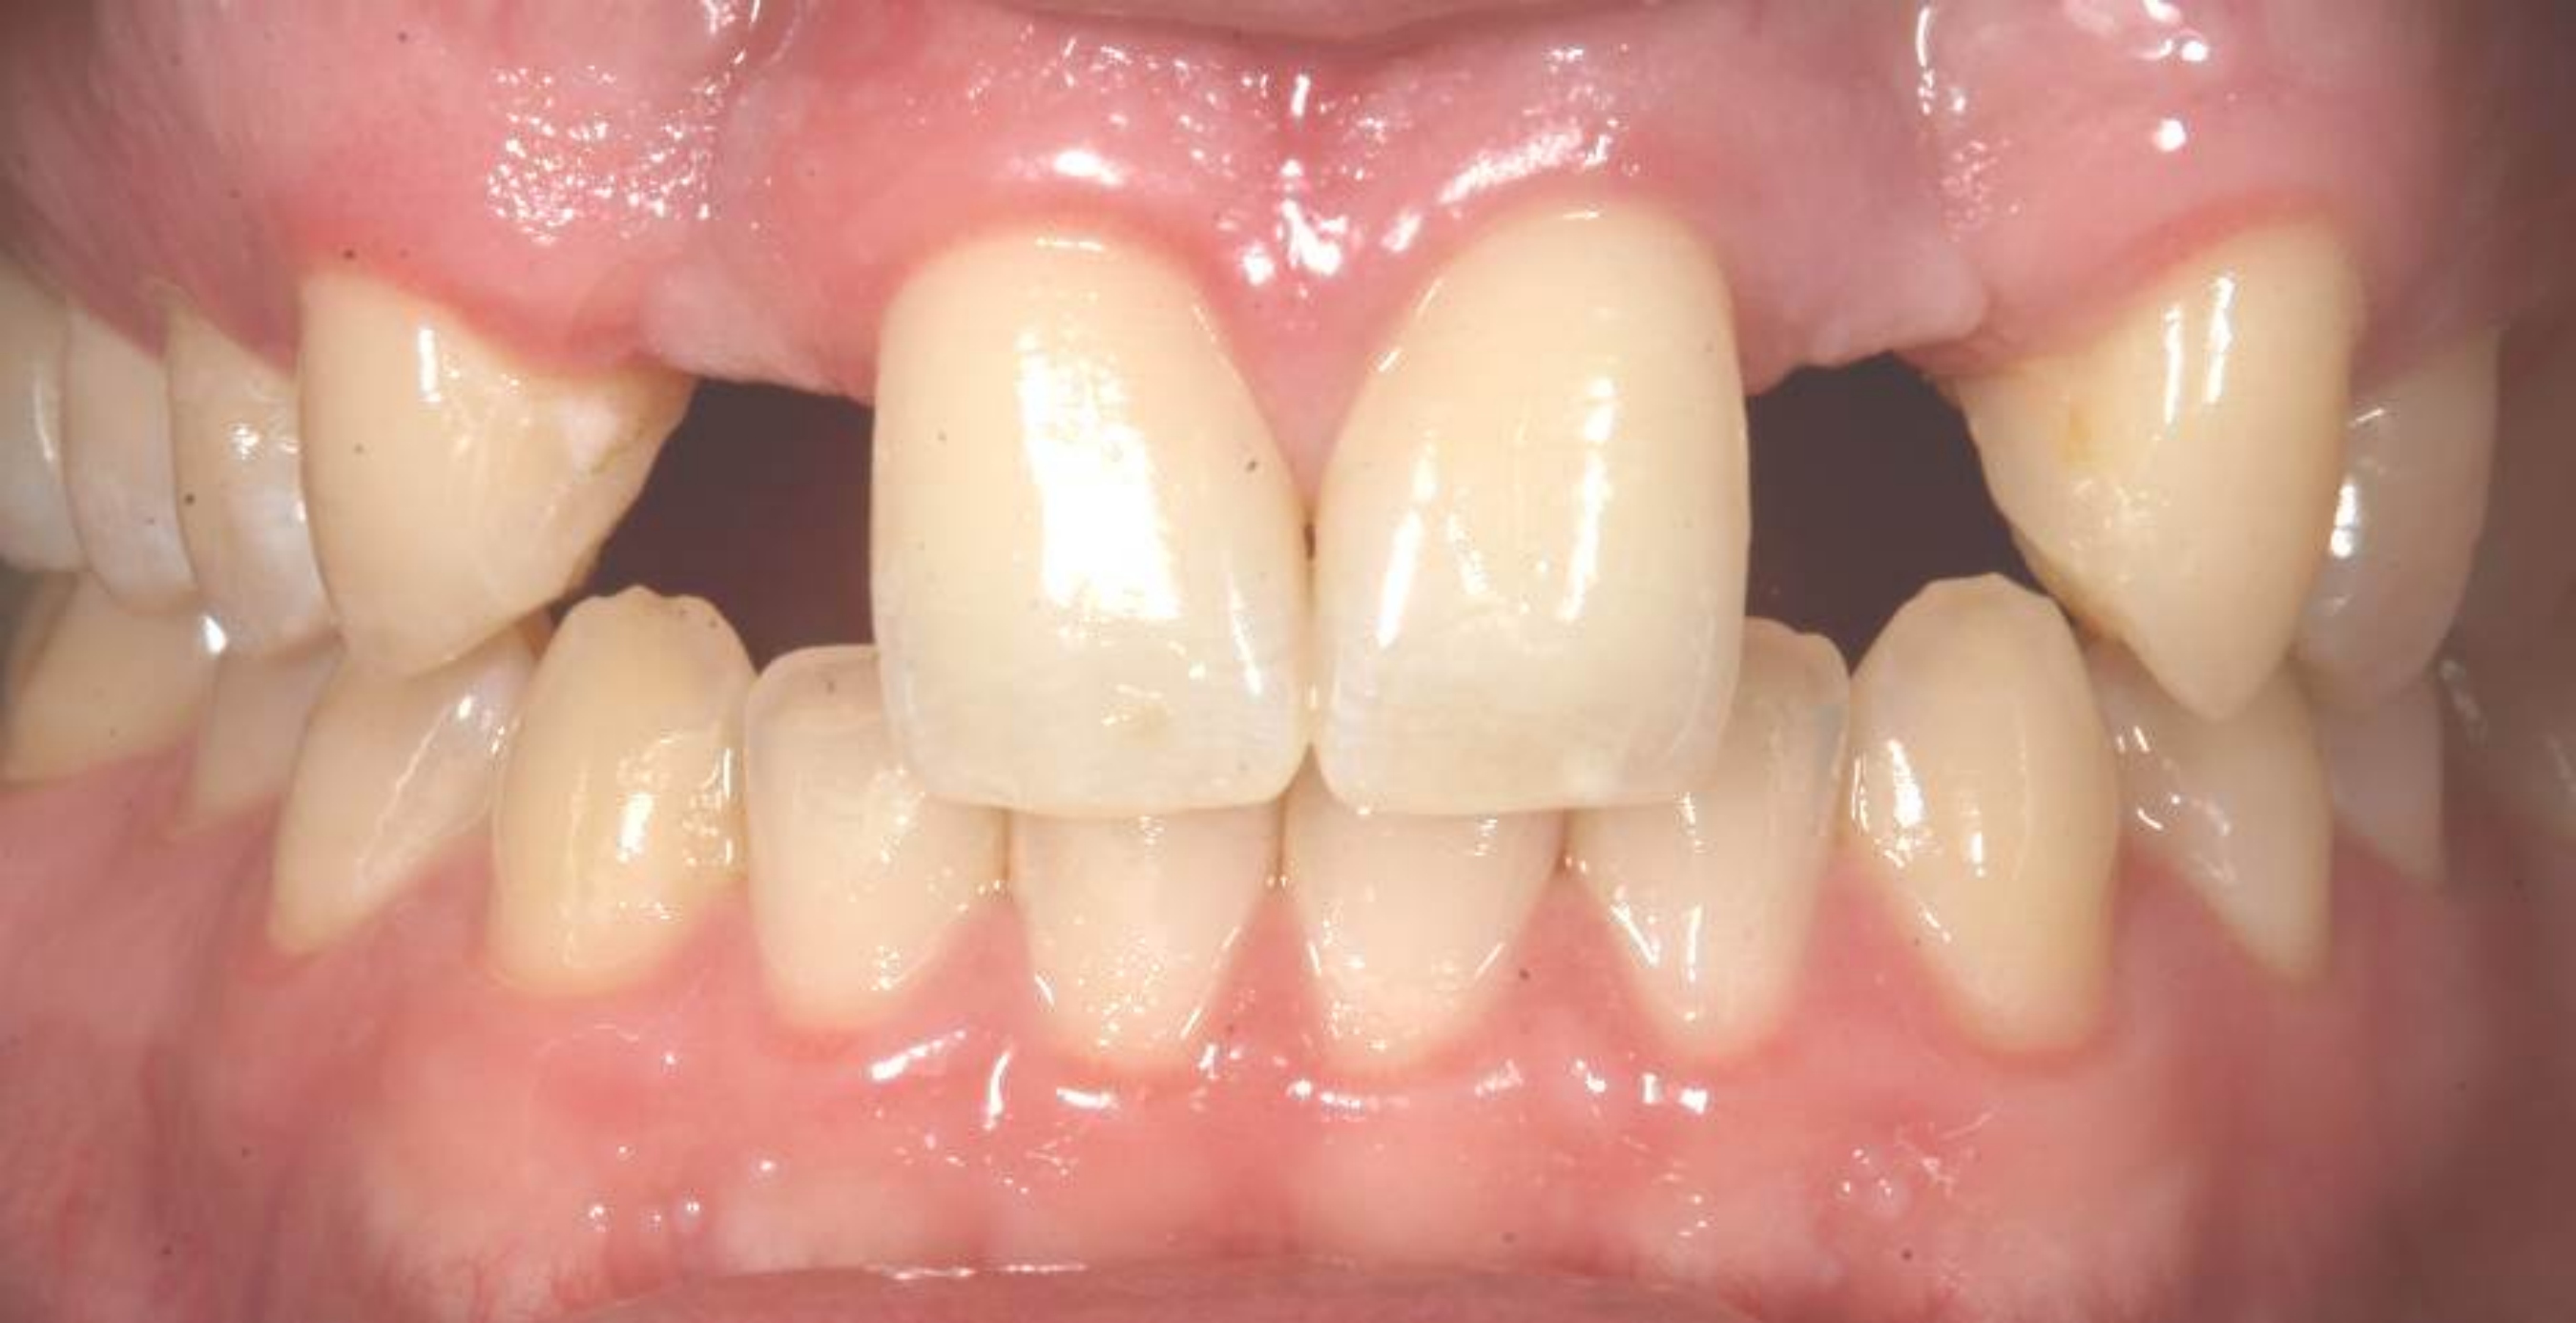

Case 3: Congenitally missing lateral incisors at the sites of teeth Nos. 7 and 10. Both sites were treated simultaneously. (Treatment at the site of tooth No. 10 is illustrated.)

Figure 19

There are numerous scenarios when a papilla-sparing incision can be advantageously used, including implant placement, the reconstruction of soft tissue and bone, or both. Figure 10 through Figure 18 and Figure 19 through Figure 25 illustrate how papillae-sparing incisions can be used to restore form and function using a nonsubmerged implant protocol. (Surgeries were performed by DT.)